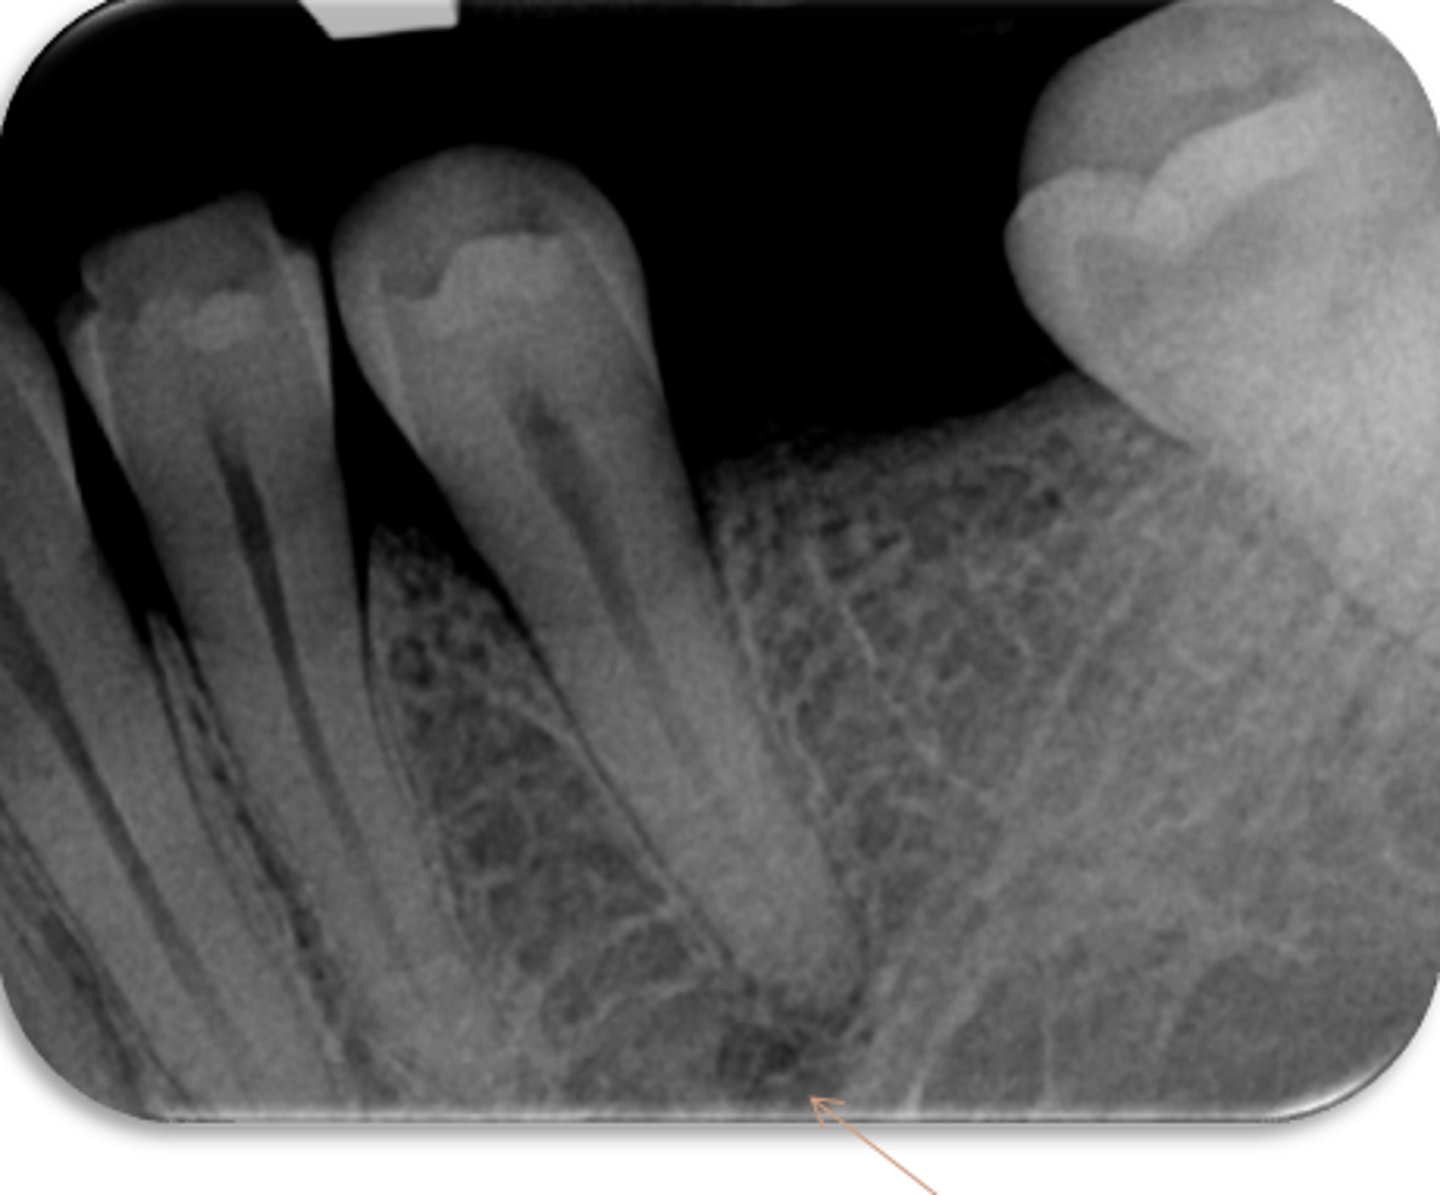

ID the structure with the purple arrow:

external oblique line

ID the structure with the green arrow:

inferior alveolar nerve canal